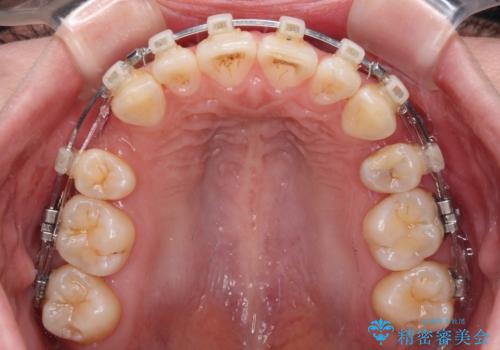

- 矯正装置

- クリアブラケット

- 2年2ヶ月

- 口を閉じたときに唇の間から飛び出してくる前歯を気にして来院された患者様です。

骨格的に上顎骨が前方位にあるため、左右の第一小臼歯を抜歯し、ワイヤー装置にて咬み合わせを整えていくこととしました。